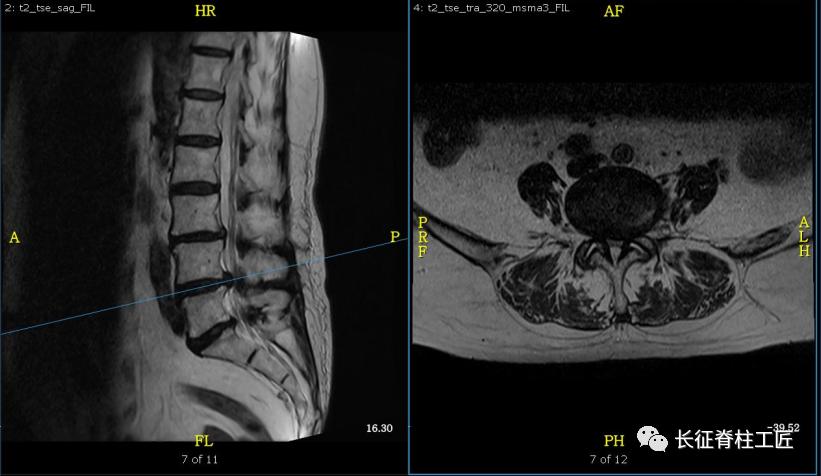

入院检查,腰部疼痛,后伸时加剧,局部压痛,双下肢肌力减退。X线检查,L4、L5骨质增生,MRI显示L4/L5、L5/S1椎间盘突出,马尾神经受压明显,被确诊为腰椎管狭窄症。

马尾神经是脊髓和周围神经的桥梁,脊髓的末端一般位于第2腰椎水平(腰椎共5节),脊髓末端就接着马尾神经,第2腰椎以下的腰椎管狭窄或腰椎间盘突出,压迫马尾神经,就会产生马尾神经综合征。